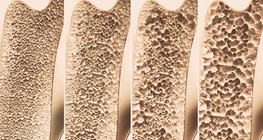

Osteoporosis is a disease of progressive bone loss, it is called a “silent" disease because there are typically no symptoms until a bone is broken.